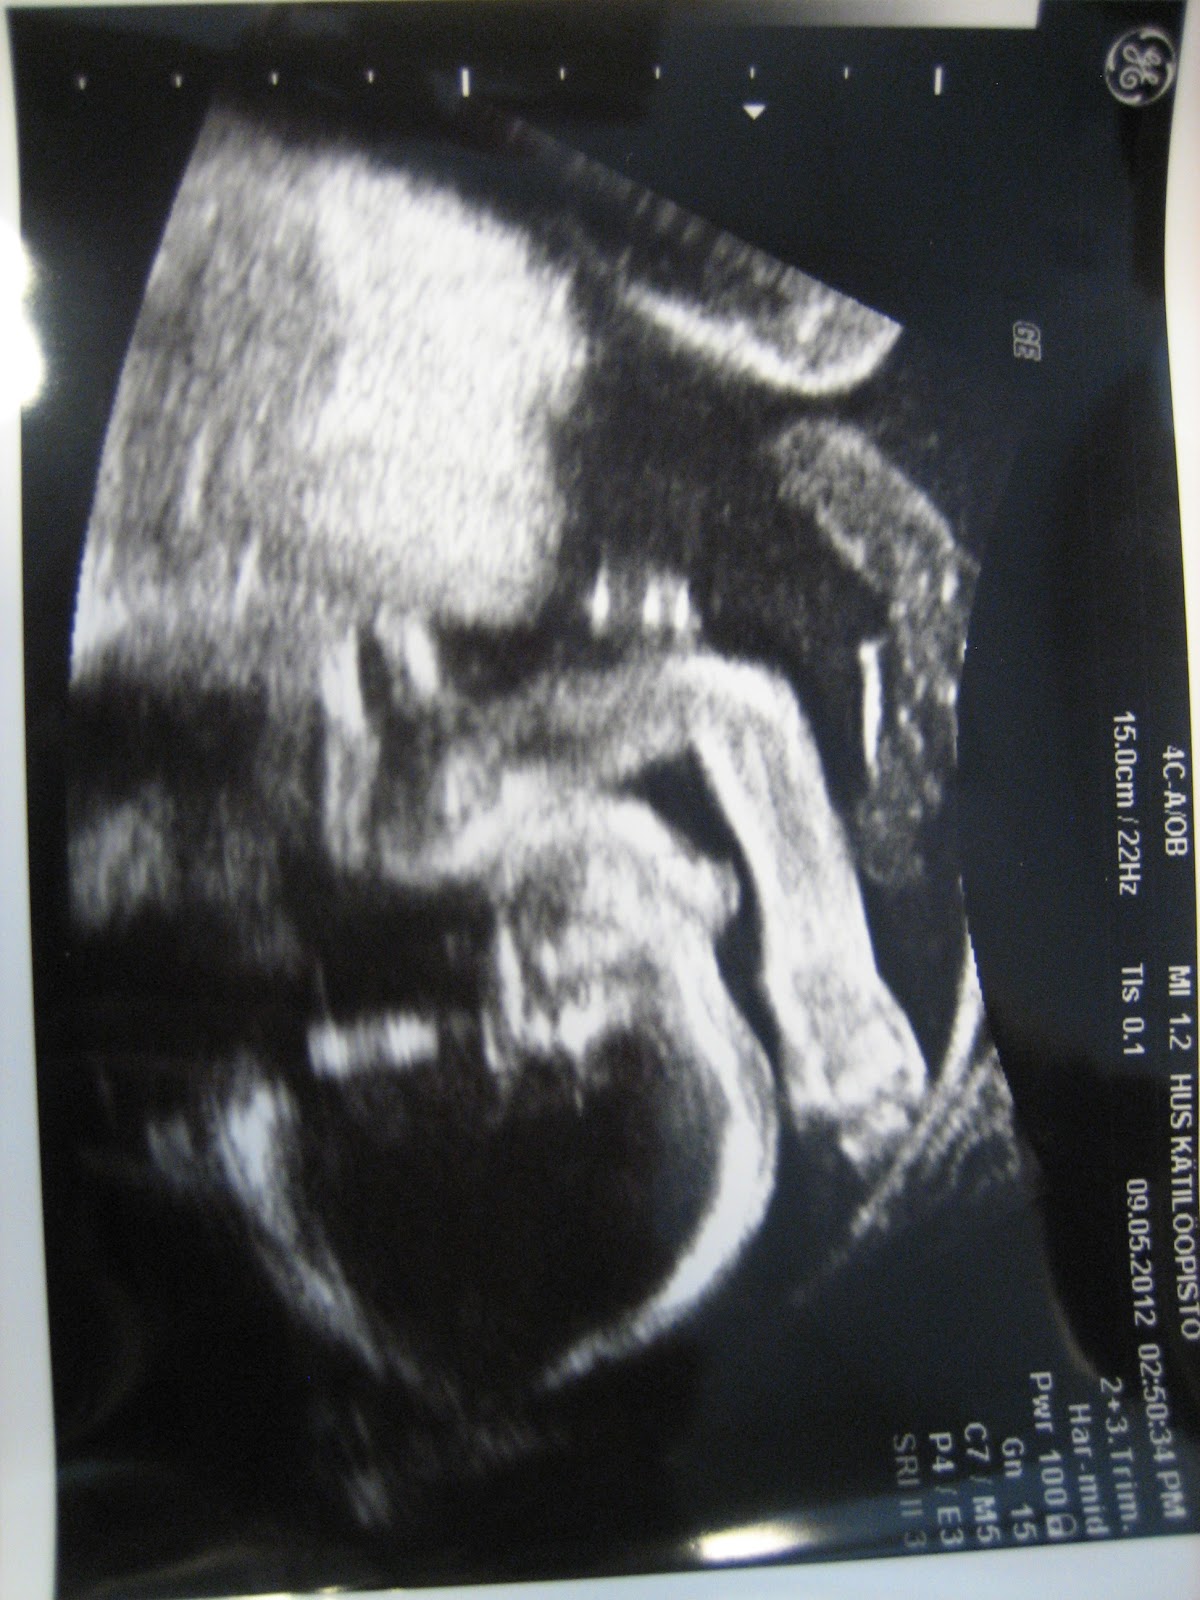

Klo 18 55 24 6 2009. Miten päin vauva on et paljonko tuntuu liikkeet. Sikiön vähentyneet liikkeet rv. Hennamami 20 maalis 2012 4 lainaus.

Uudelleensynnyttäjä tunnistaa yleensä lapsen liikkeet hieman aiemmin. Rakenneultrassa rv 24 kätilö tuumasi että olipas mojova potku tunsitkos. Sikiön liikkeet rv 40. Itsellä oli kanssa aikoja jolloin ei kuulunu juuri liikkeitä ja vastaavanlainen huoli oli myös itsellä tänään tuli täyteen 19 raskausviikkoa ja 20 pyörähti käyntiin liikkeet tuntuu nyt välillä ylempänäkin eikä aina tuolla alhaalla.